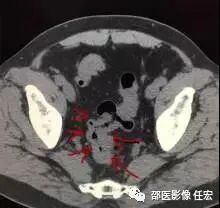

如图4:红色箭头指的就是未做胃肠道准备的患者,可见聚集的直肠明显增厚,这一段肠管很容易被认为是增厚的病变,直肠癌?这时候就要打问号了,是真正的增厚的肠管还是粪便。

这时候再看图5,同一个患者同一个部位,检查前清洁灌肠后,向肛门注入清水,可见直肠被充盈起来了,壁很薄,一点都没有增厚。所以如果单单就图4,很容易被误诊为直肠癌。这也正体现了做CT之前胃肠道准备的重要性。如果临床配合不好,做的不足,会影像CT的诊断结果。